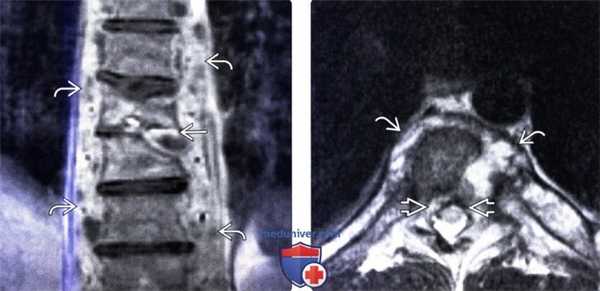

(Слева) Фронтальный срез, Т1-ВИ с КУ (бластомикоз): сужение и деструкция межпозвонкового диска грудного отдела позвоночника, патологические изменения сигнала костного мозга тел позвонков и компрессионный перелом позвонка. Видны распространенные флегмонозные изменения паравертебральных тканей и гетерогенное контрастное усиление сигнала патологически измененного межпозвонкового диска.

(Справа) Аксиальный срез, Т2-ВИ (бластомикоз): гиперинтенсивная паравертебральная флегмона. Объемное образование в вентральном отделе эпидурального пространства несколько оттесняет спинной M03г патологического изменения сигнала спинного мозга не отмечается.

(Слева) Диффузное патологическое снижение интенсивности Т1-сигнала (кокцидиомикоз) отражает диффузную анемию и гиперплазию ± инфильтрацию костного мозга. Обратите внимание на деструкцию тел и задних элементов среднегрудных позвонков с распространением процесса на паравертебральные ткани и сохранением межпозвонковых дисков.

(Справа) Сагиттальный срез, Т1-ВИ с КУ (кокцидиомикоз: превертебральный абсцесс, характеризующийся периферическим контрастным усилением сигнала, на фоне хронического течения инфекционного процесса. Тела С7 и Т1 позвонков разрушены, при этом межпозвонковые диски относительно сохранны, в вентральной части эпидурального пространства определяется флегмона.